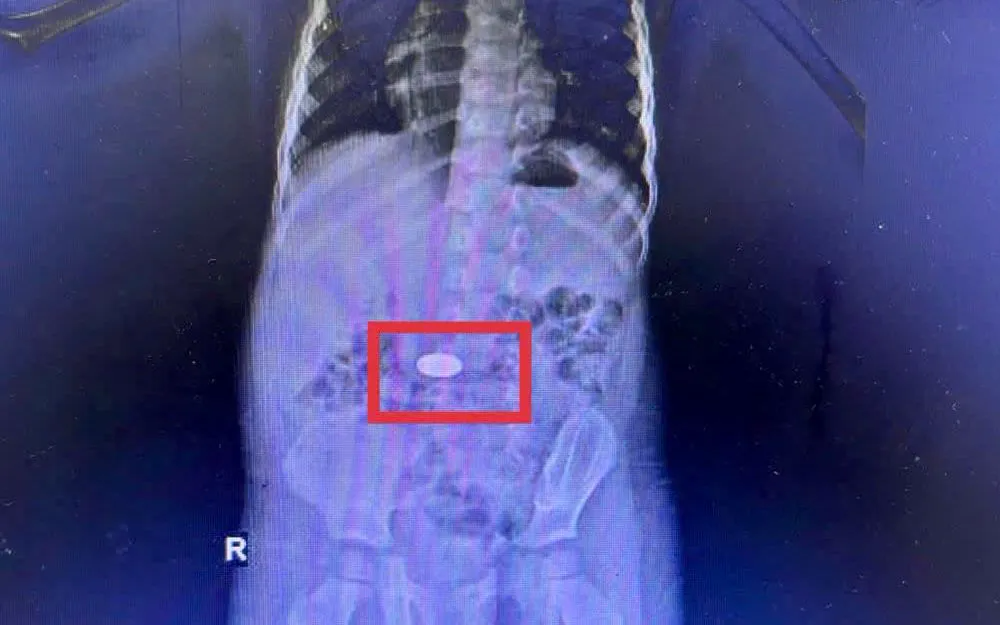

Kết quả siêu âm tim cho thấy trẻ bị còn ống động mạch lớn - dị tật khiến máu chảy bất thường từ động mạch chủ sang động mạch phổi, gây giãn buồng tim trái và suy tim nặng. Hội chẩn liên khoa xác định phẫu thuật thắt ống động mạch là phương án duy nhất để cứu sống trẻ.